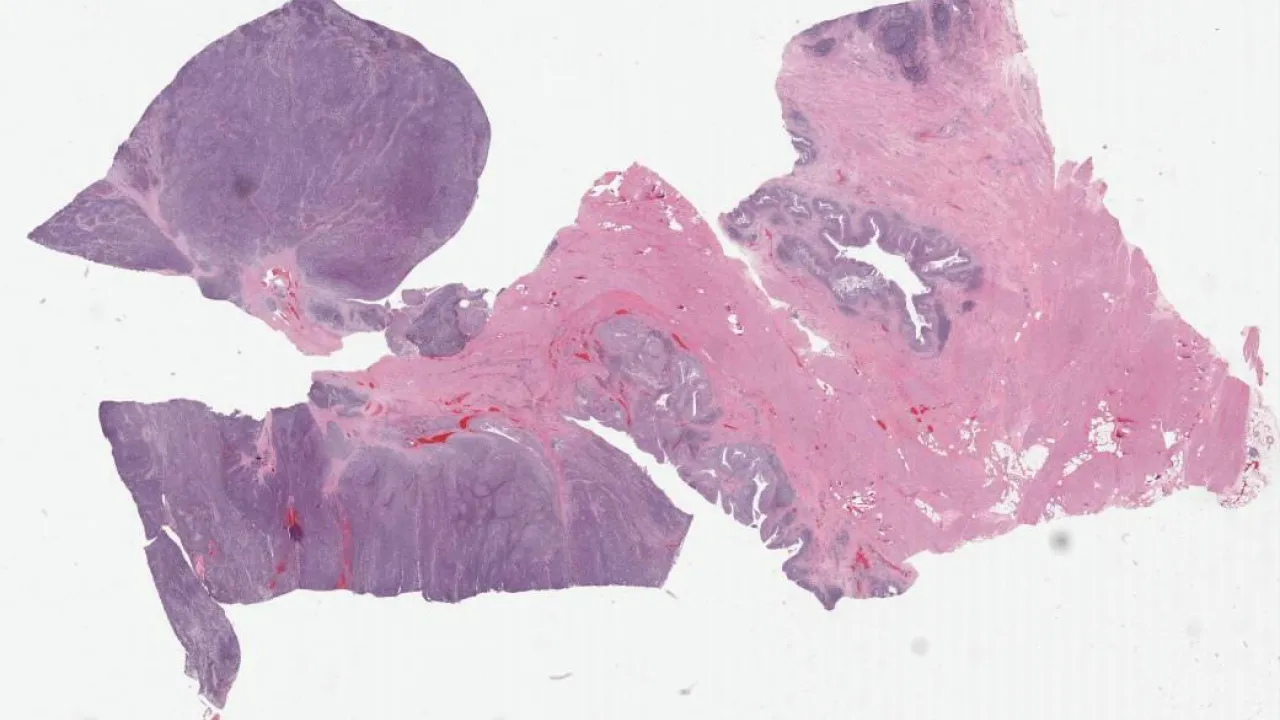

Lower Urinary Tract and Male Genital System

Subscribe to Lower Urinary Tract and Male Genital System